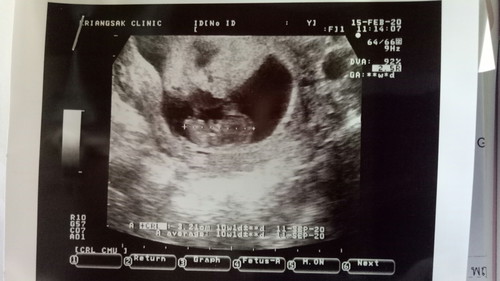

คบกับแฟนมาเปนปีมีทะเลาะกันบ้างตามประสาง้อกันดีกัน แต่ก้รักกันดี จนมาวันนึงบอกแฟนว่าท้องโอเคแฟนรับได้ แม่แฟนรับได้ แต่ชีวิตคู่คำว่าแฟนมันก้ไม่ได้ดีราบรื่นเสมอไป เราท้องได้7วีคแฟนหรือสามีเริ่มไม่สนใจเรา เราพยายามนะ พยายามทน พยายามเดินเข้าหา แต่กลับเปนสามีเราที่เฉยแร้วเดินออกห่าง จนมาวันนี้ตอนนี้ เราตัดสินใจบอกสามีไปว่าต่างคนต่างอยู่ พี่ไม่มีสิทธิ์ในตัวนู๋กับลูกอีกต่อไปในเมื่อพี่เลือกที่จะทิ้งพวกเรา ถามว่าเสียใจมั้ย เสียใจนะ แต่ก้ต้องสู้ เพื่อ...ลูก #คุณแม่เลี้ยงเดี่ยว ไม่ว่ายังไงแม่คนนี้ก้จะไม่ทิ้งลูกเหมือนที่พ่อเค้าทิ้งเรา รักลูกนะ